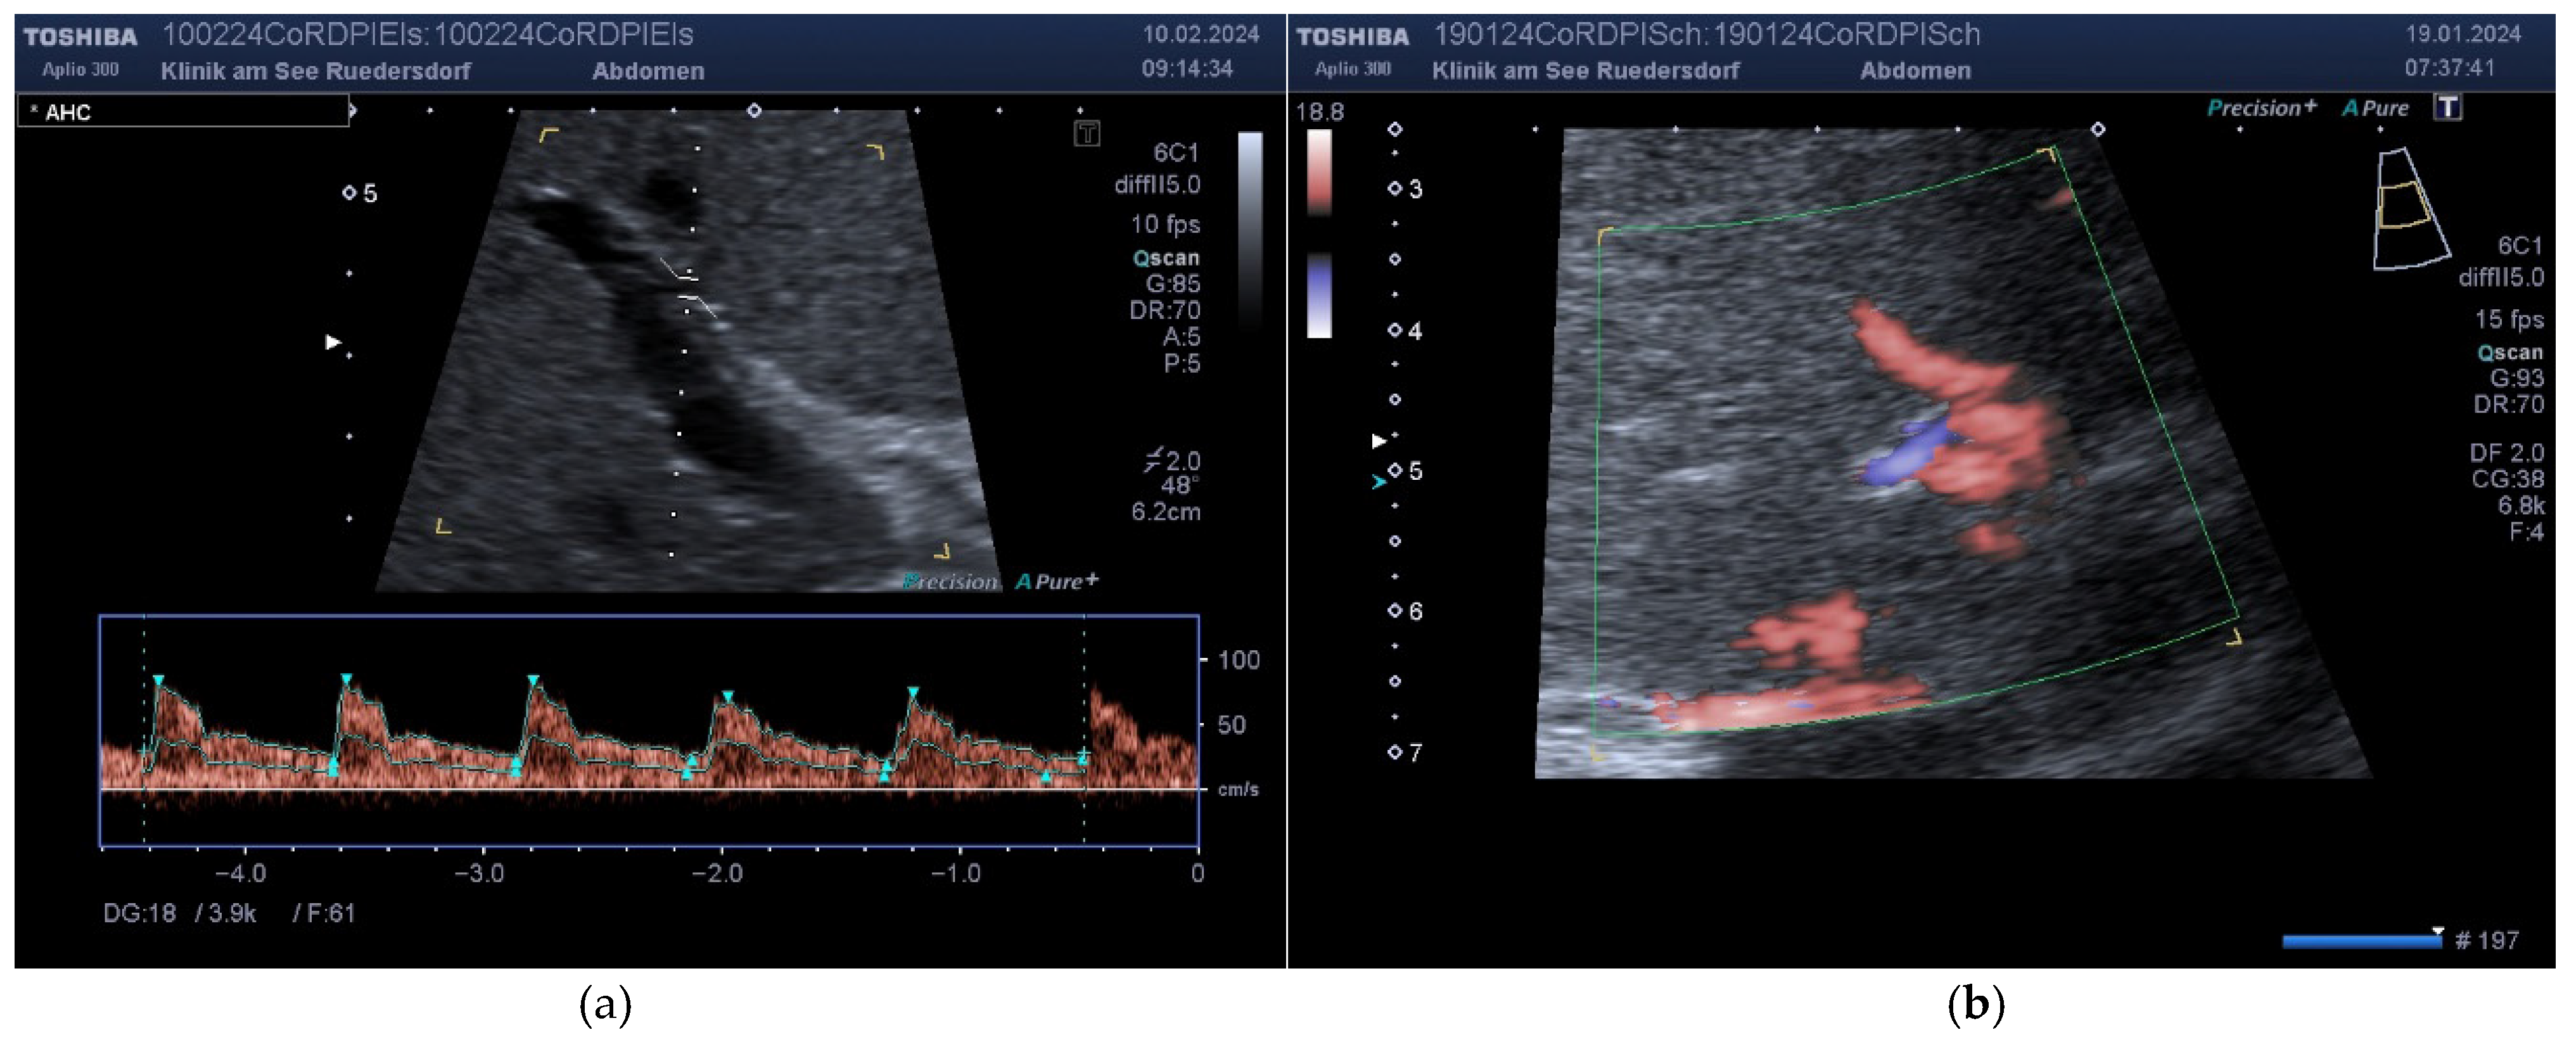

2.3.1. Determination of Vessel Diameter

2.3.2. Location of the Probe, Insonation Angle, and Doppler Window